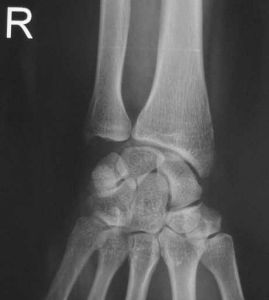

月骨脫位--CT月骨周圍脫位者,月骨留在原位,其他腕骨向背側移位,並向橈側變位形成畸形。X線正位片顯示,脫位的月骨呈三角形(正常月骨應為四方形)。且投影與頭狀骨下端重疊。側位像顯示,月骨脫向掌側,半月形凹面也轉向掌側。

月骨脫位--檢查(1)X線正位片:可見腕骨排列紊亂,頭狀骨與月骨影重疊,舟月間隙增大,舟骨長軸變短,呈皮質環征或舟骨鏇轉,月骨脫位失去四邊形結構,呈三角形影。

月骨周圍脫位線正位片可見腕骨弧線中斷頭狀骨與月骨橈骨與舟骨投影重疊加重,腕中關節間隙消失,舟月骨間關節間隙變寬,月骨周圍腕骨及橈尺骨遠端可有骨折,X線側位片可見舟骨掌屈加大,縱軸與橈骨縱軸近乎垂直,近極位於橈骨遠端關節面背側緣或掌側緣上,月骨與橈骨遠端關係正常,橈月關節間隙無明顯異常,其餘腕骨向背側或掌側脫位其中,頭狀骨最突出。頭由月骨遠側凹面內脫出,位於月骨背側或掌側月骨周圍腕骨如有骨折。其遠側段多脫向背側或掌側,而近側段仍滯留在原位與月骨保持正常關係。

月骨脫位X線正位片可見月骨輪廓,由梯形變為三角形。周圍關節間隙不平行或寬窄不等,側位見月骨掌側脫位輕者,月骨仍位於橈骨遠端凹面內,掌屈過度,橈月關節背側間隙變寬,頭狀骨與月骨背側面相對重者,月骨掌屈大於90°進入腕管內與橈骨遠端、頭狀骨完全分離。月骨周圍脫位與月骨脫位X線片影像雖然顯著,但漏診率至今仍居高不下。恐怕與X線側位片骨影相互重疊,單一腕骨輪廓難於分辨有關。診斷困難者可做CT檢查。

根據X線片檢查不僅可以明確診斷,尚可對脫位類型進行分類。正常時腕關節正位片上月骨呈四方形,位於橈骨與頭狀骨之間,在側位片上頭骨、月骨、橈骨三者呈直線關係排列,上述關係的異常很易在X線上發覺,因此診斷並不困難。